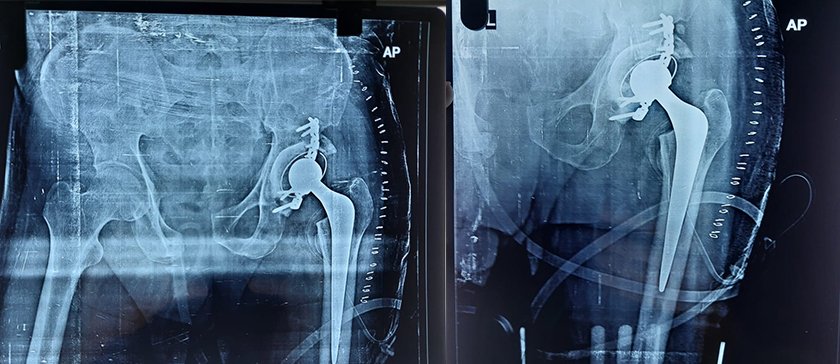

Hip Joint Replacement - The Procedure

When the surgical team is ready, you’ll be taken to the operating room. There you’ll be given anesthesia. The anesthesia will help you sleep through surgery, or it will make you numb from the waist down. Then an incision is made, giving the surgeon access to your hip joint. The ball is cut from the thighbone, and the surface of the old socket is smoothed. Then the new socket is put into the pelvis. The socket is usually press-fit and may be held in place with screws or cement. A press-fit prosthesis has tiny pores on its surface that your bone will grow into.

The new hip stem is inserted into the head of your thighbone. After the stem is secure in the thighbone, the new ball and socket are joined. The stem of the prosthesis may be held with cement or press-fit. Your surgeon will choose the method that is best for you. After the new joint is in place, the incision is closed with staples or stitches.

Today, many patients who have hip replacement surgery can move their joint more easily, have less pain and are able to walk more comfortably for up to 20 years after surgery.